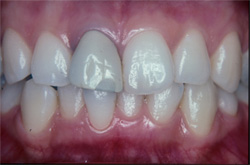

| インプラントの上のクラウンにより、あなたの咀嚼機能と自然な風貌が回復するでしょう。 |